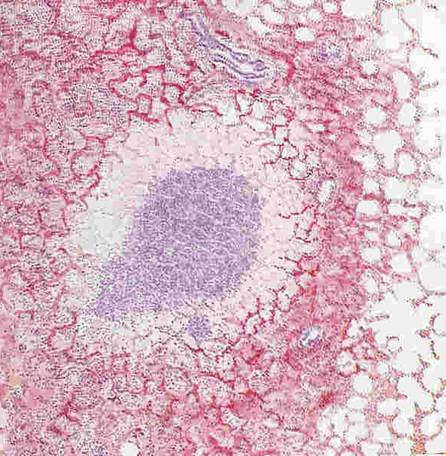

Рис. 32. Туберкулезный очаг в легком лошади. Очаг молодой, поэтому в центре поражения видна масса лейкоцитов, чьи ядра придают этому участку фиолетовый цвет, по периферии – разрастающаяся фиброзная ткань, окрашенная в нежно розовый цвет. По периферии – выраженная артериальная гиперемия.